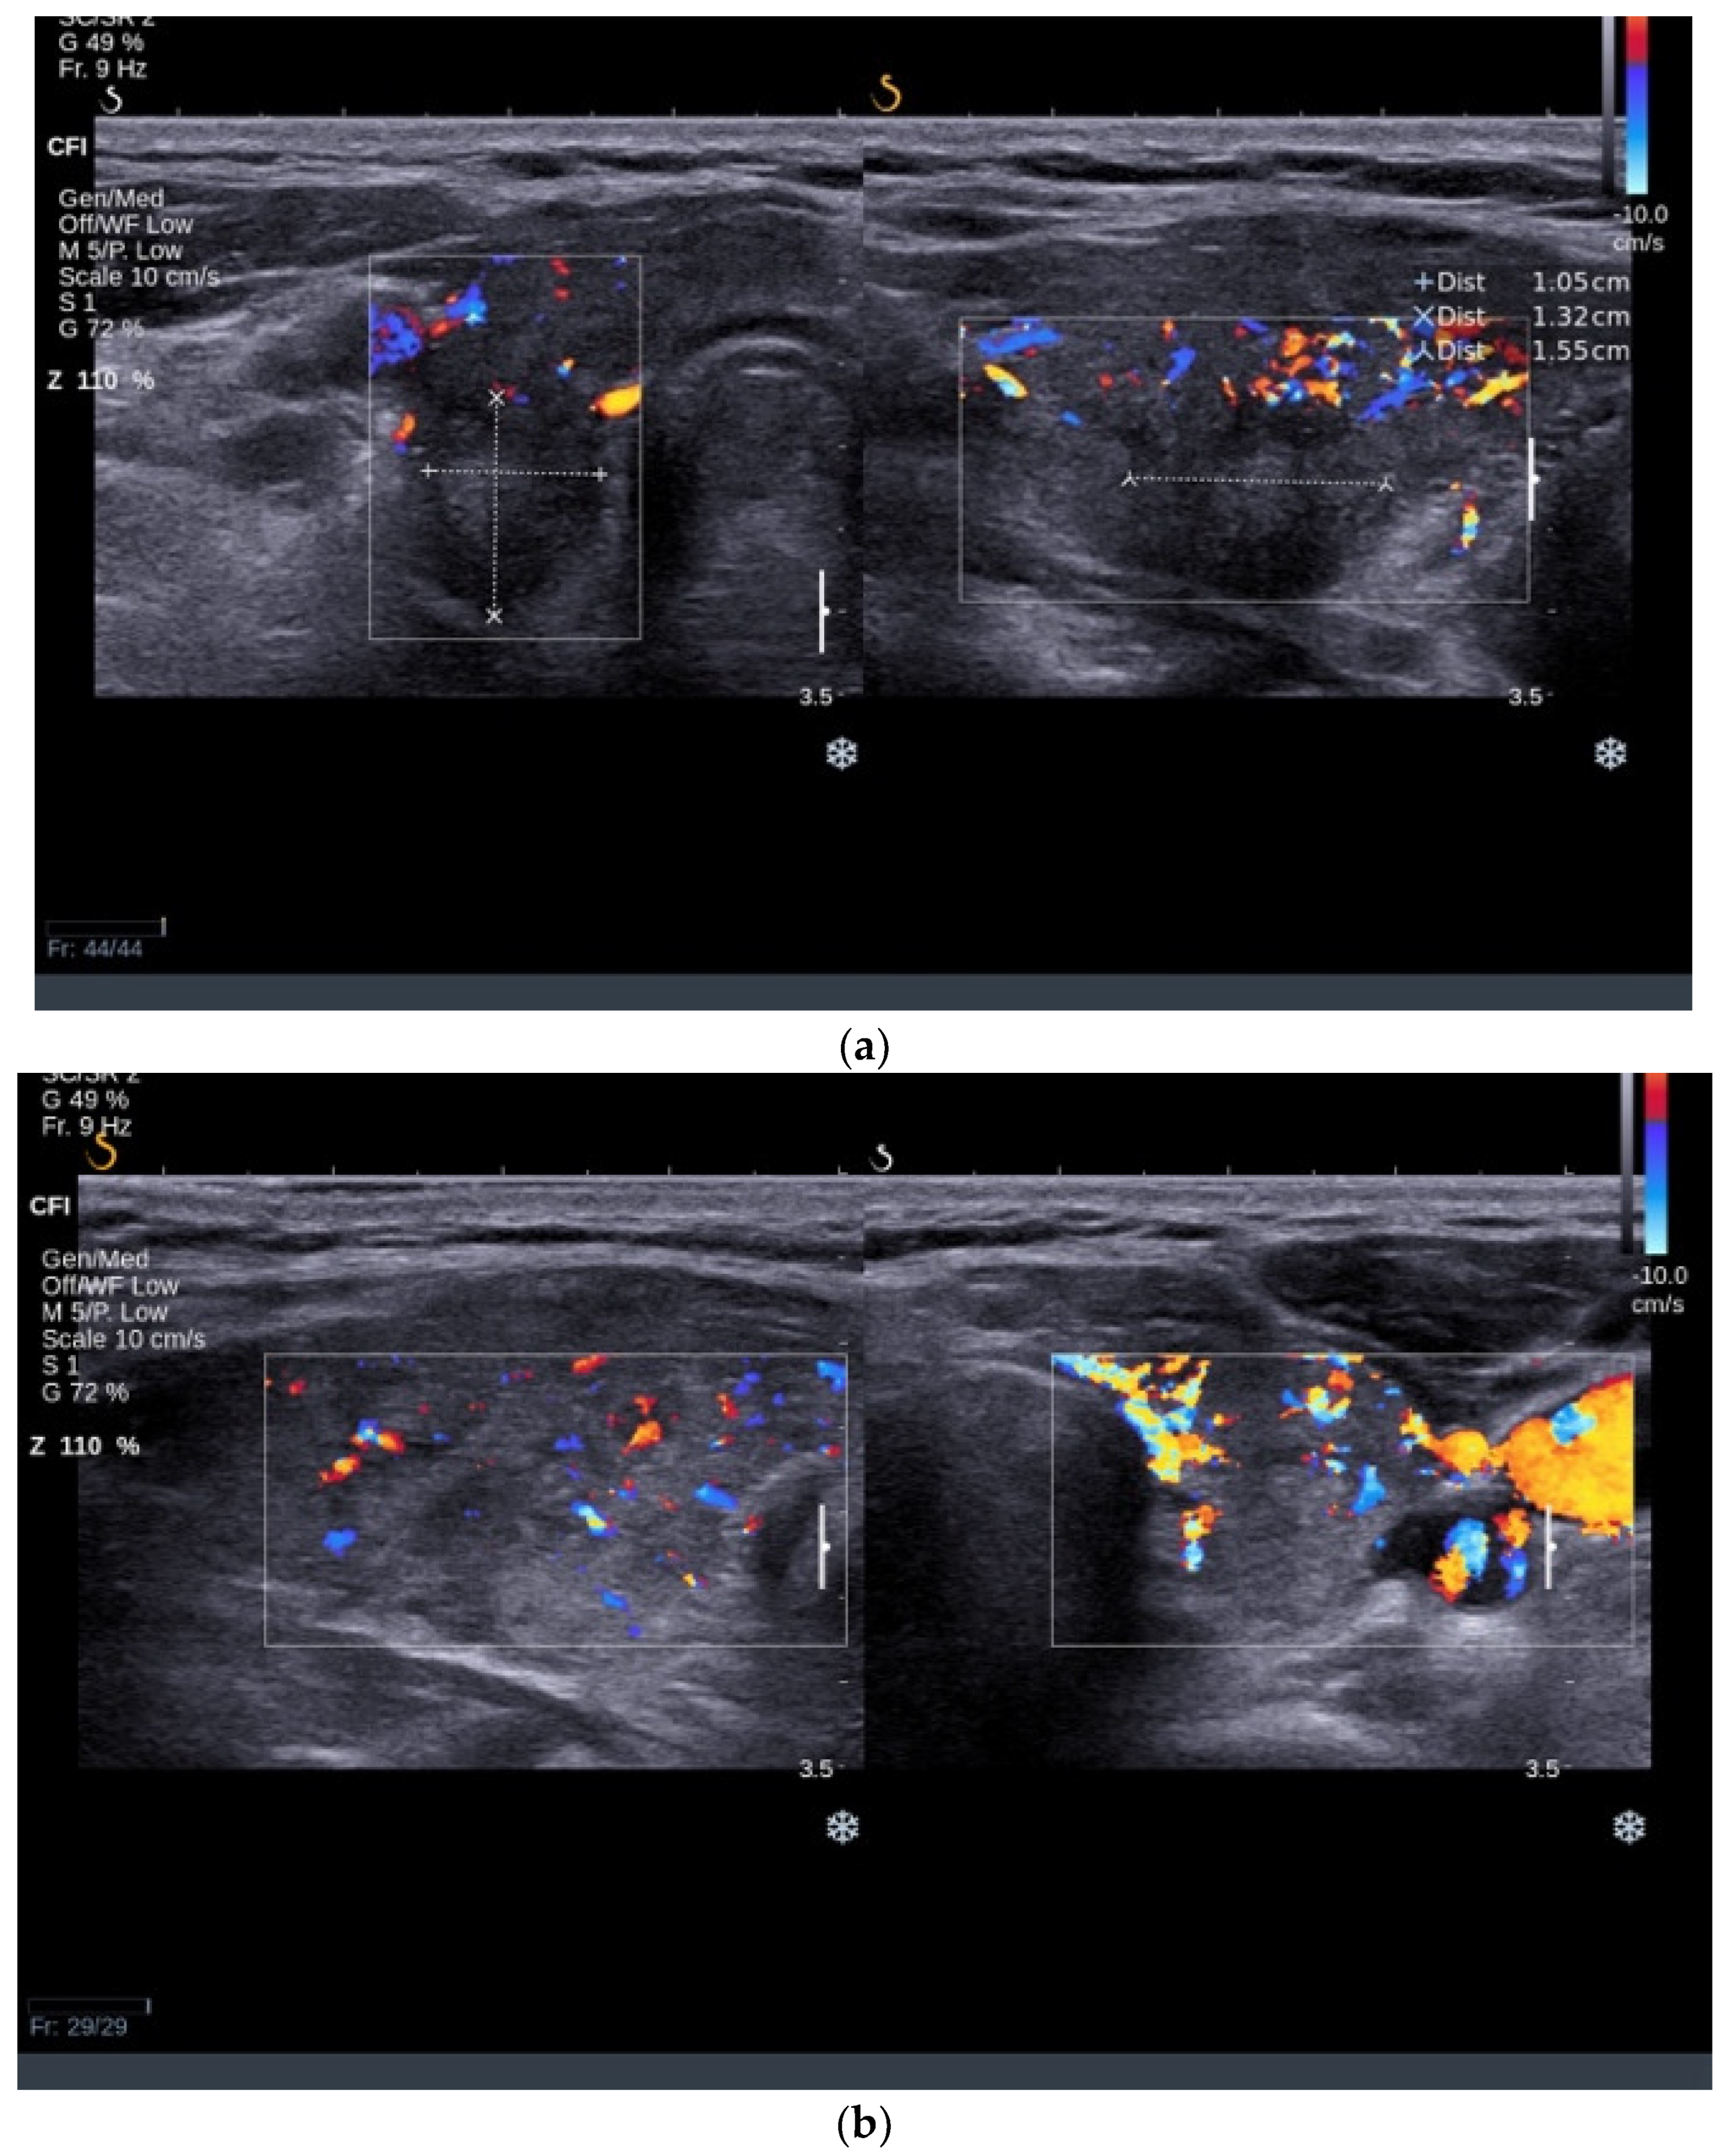

3.2.2. Thyroid Ultrasound

3.3.2. Thyroid Ultrasound